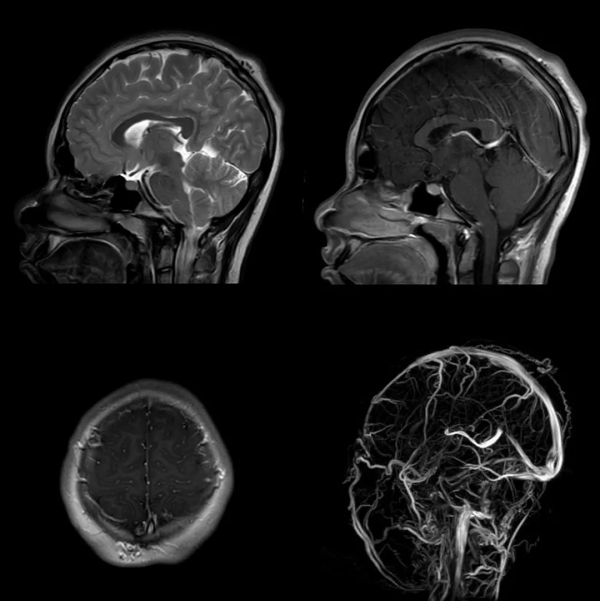

頂突閉鎖:它們是由腦膜和殘留纖維組織等組成的良性畸形病變,通常位於中線,被面板覆蓋。MRI 是能夠很好的觀察內容物,靜脈血管造影 MRI 可能顯示偶然的原始鐮狀靜脈持續存在,以及靜脈竇的其他異常

矢狀位 T1WI 和矢狀位 T1WI MIP 增強顯示頂部皮下結節(綠箭頭),增強與上矢狀竇相通,與永存鐮狀竇共存(紅箭頭)

枕骨孔樣缺損,增強與竇匯溝通

頂部皮下腦脊液訊號,與永存鐮狀竇共存